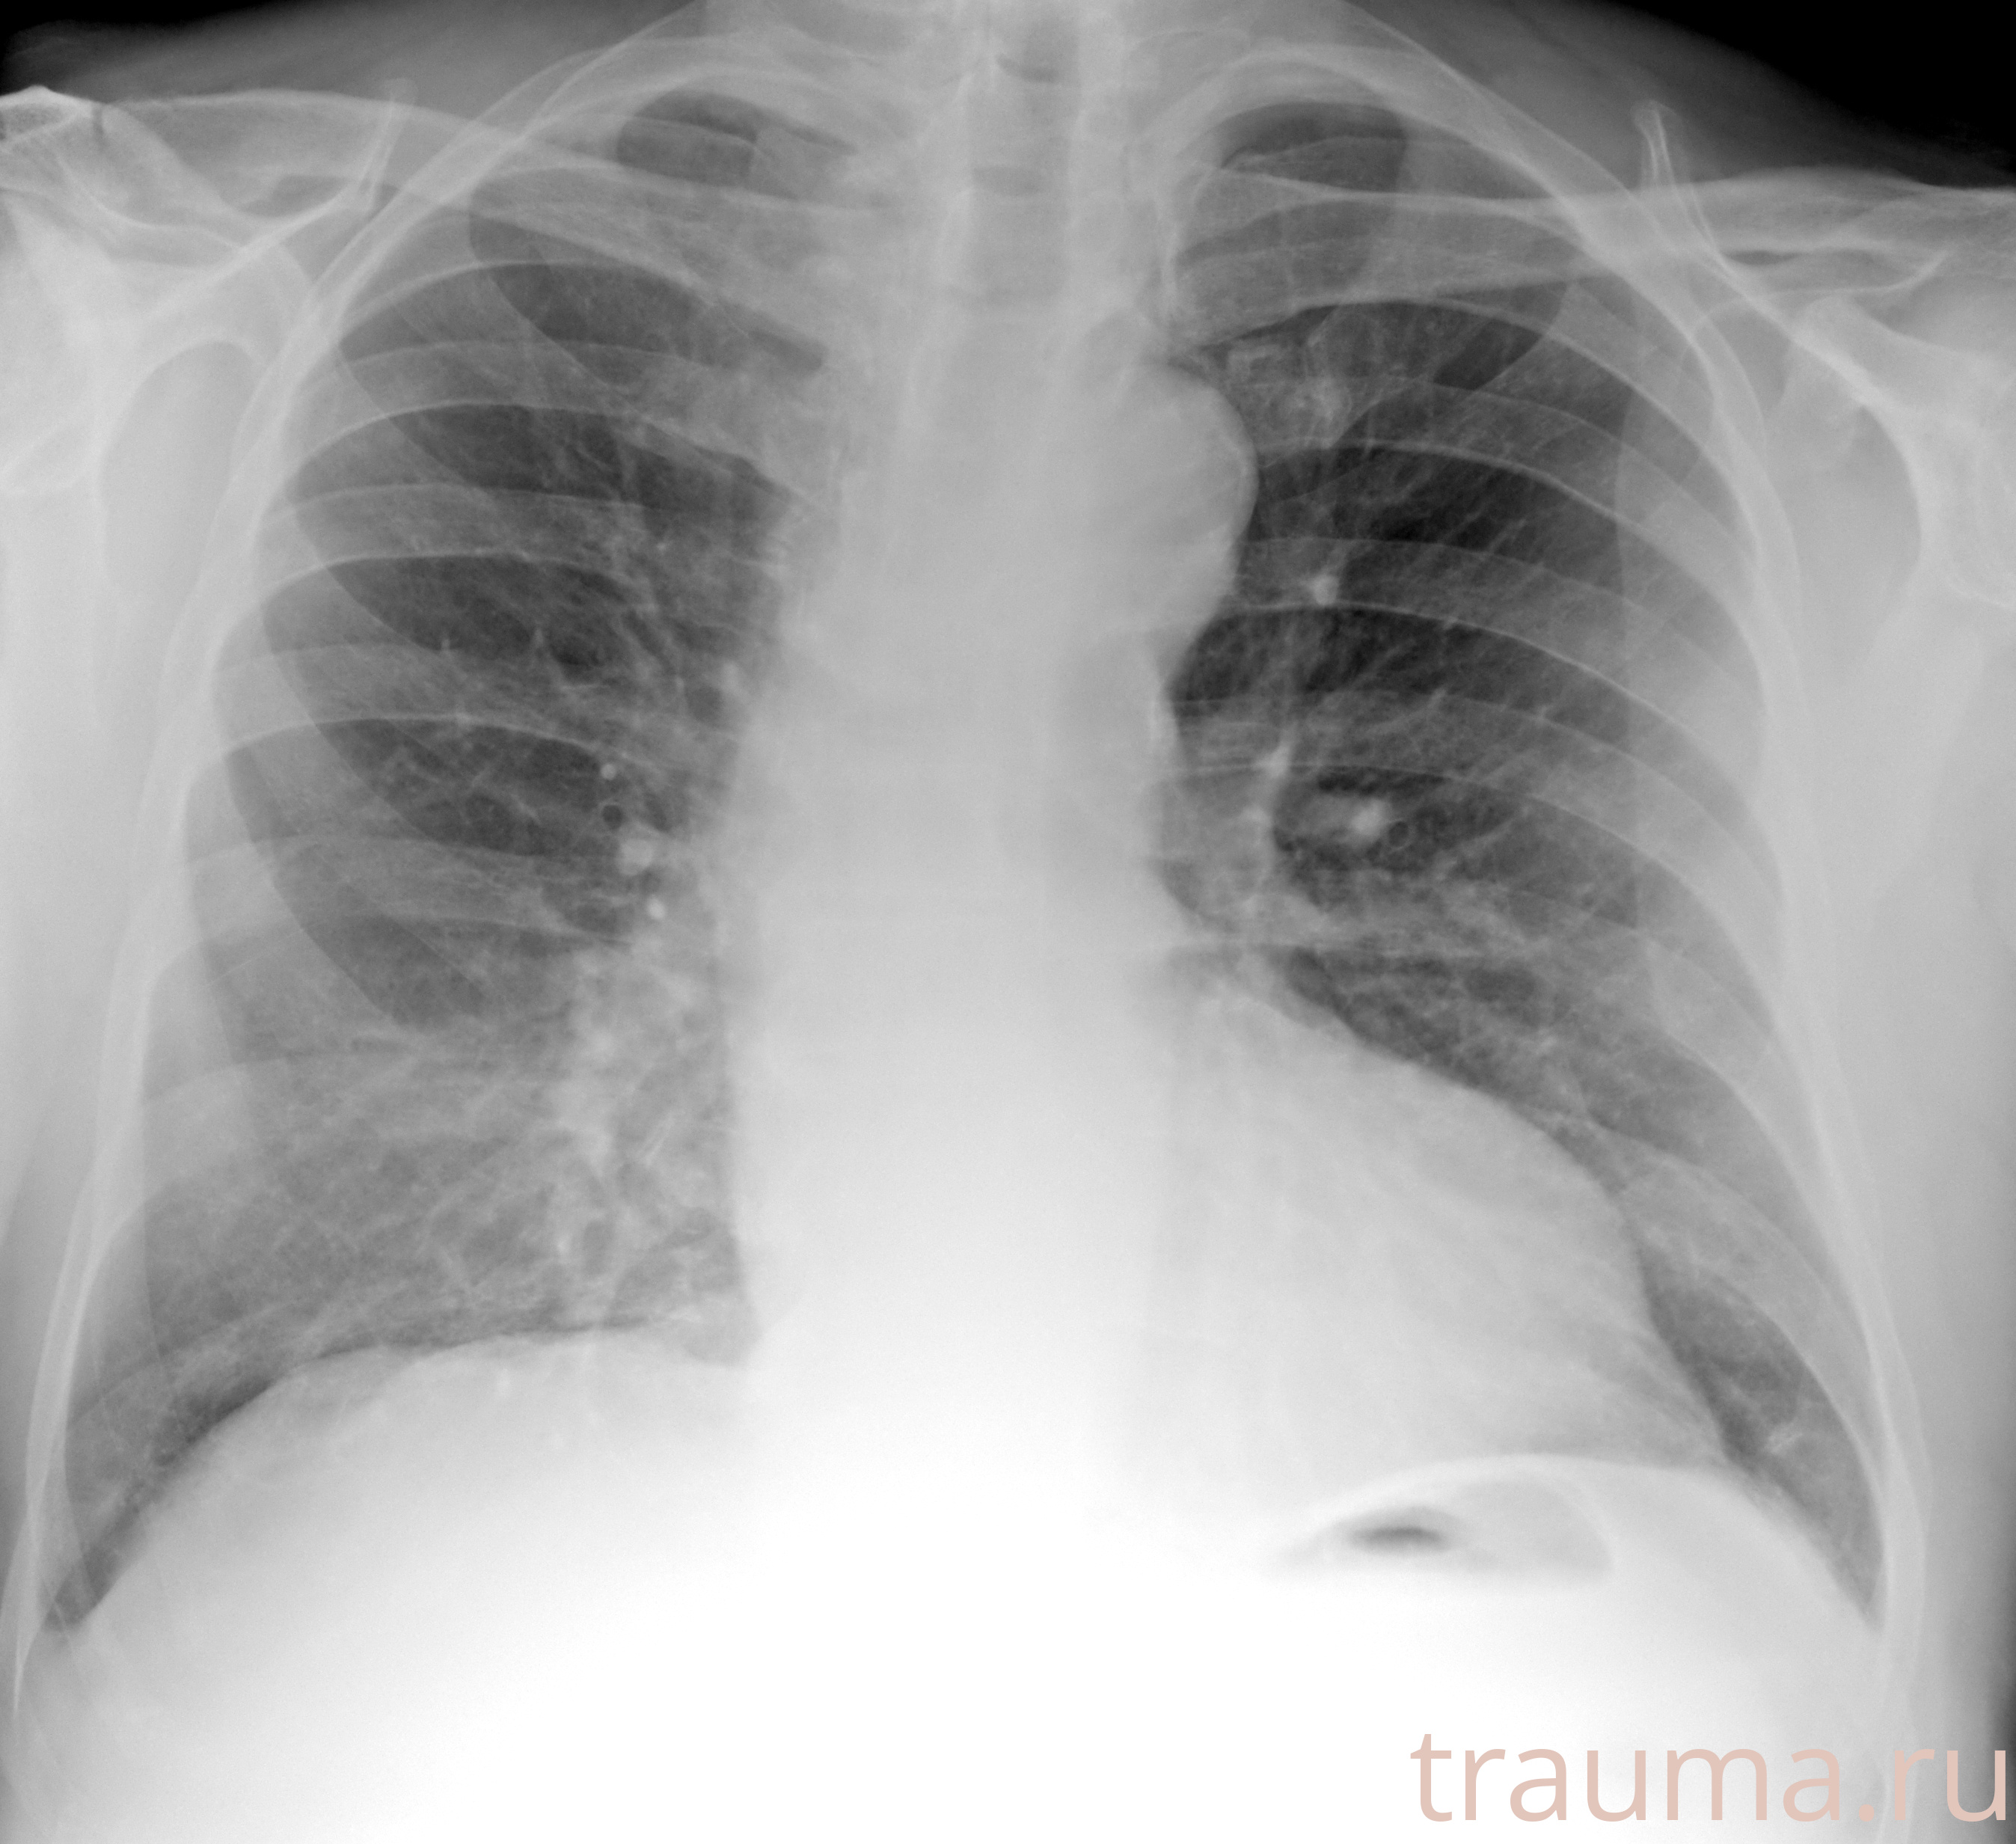

Рентгенограммы

Рентген на дому: по вашему адресу приезжает врач-рентгенолог, травматолог-ортопед с мобильным рентгеновским аппаратом, проводит диагностику травмы или заболевания, делает необходимые рентгенограммы, дает рекомендации по дальнейшему лечению. Получить качественные снимки в домашних условиях возможно благодаря уникальной методике, разработанной МосРентген Центром для института  Склифосовского

при переломе шейки бедра и пневмонии от компании МосРентген Центр - партнера Института имени Склифосовского